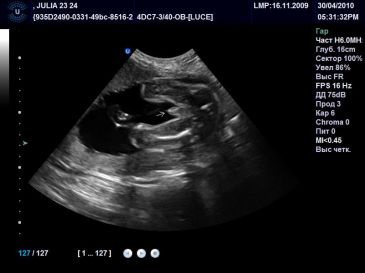

Здравствуйте, срок 13 +3 недель . Эти фото с первого скрининга) Как думаете это пацан?) я конечно мечтаю о девочке 🎀 и надеюсь, но кажется мне видно писюнчик ))) Узистка пол определила , сказала по углу видно и сравнила свои . . .

Рассмотрим фото мальчика на сроке гестации 5 месяцев . На снимке 4d видно, что пенис расположен под углом 30° к спинке ребенка . . . . При проведении первого скрининга (11-13 недель) точность не высока . . .

Здравствуйте, срок 13 недель . Эти фото с первого скрининга) Как думаете это пацан?) я конечно мечтаю о девочке 🎀 и надеюсь, но кажется мне видно писюнчик ))) Узистка пол определила , сказала по углу видно и сравнила свои . . .